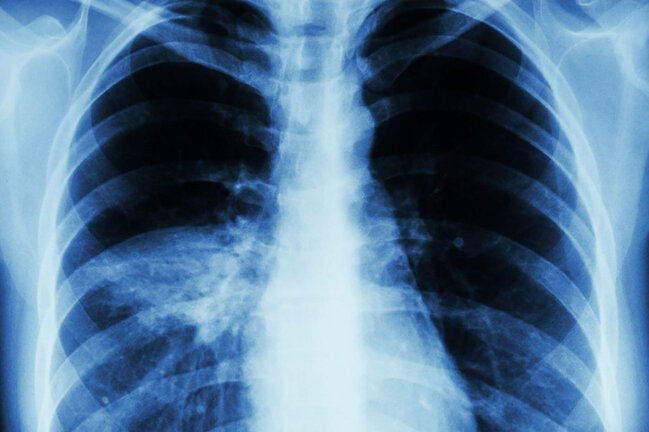

Gizli pnevmoniyanın ilk 6 əlaməti – Dərhal həkimə müraciət edin

Əgər pnevmoniya ilk başda aşkar edilərsə, düzgün müalicə ilə qısa müddətə ram edilə bilər.

Hazırda koronavirus pandemiyası vəziyyətində yaşadığınız üçün, ağciyərlərlə bağlı istənilən kiçik simptoma diqqətli olmağınız lazımdır.

Medicina.az pnevmoniyanın ilk 6 əlamətini təqdim edir.